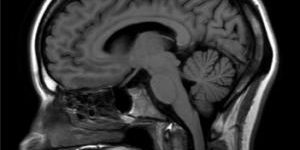

La tecnología envuelta en la máquina MRI permite hacer estudios avanzados de neuroimágenes, el corazón, las articulaciones y la columna vertebral, entre otras áreas del cuerpo. “Como el equipo tiene tecnología que es bien sofisticada, las imágenes que se producen son mucho mejores. Y en la radiología, mientras mayor sea la resolución de la imagen, mayor es tu capacidad de hacer un diagnóstico que sea preciso”, explicó el doctor Edgar Colón, Decano de la Escuela de Medicina.